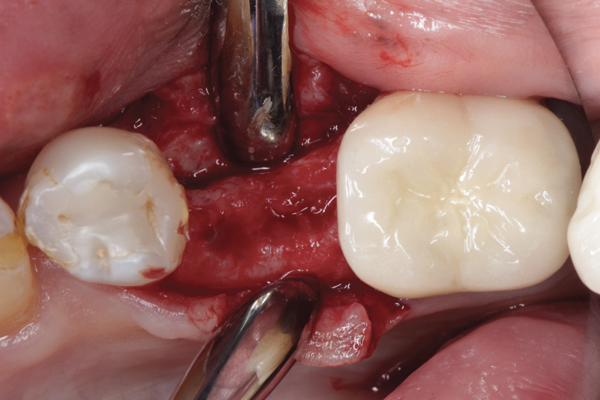

Fig 17. Bone graft was placed in the socket and a d-PTFE barrier was used to cover the graft. The bone graft material was placed beyond the alveolar housing to accommodate shrinkage of graft material and to facilitate attaining a wide alveolar ridge. The barrier was removed after 6 weeks.

Figure 17

Fig 18. Healed ridge exposed after 6 months.

Figure 18

Fig 19. Implant inserted into healed ridge.

Figure 19